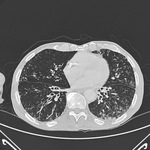

Bronquiectasia

Tomografia computadorizada do tórax com a presença de anel de sinete à esquerda

Dos arquivos do Dr. Sangeeta M. Bhorade; uso autorizado